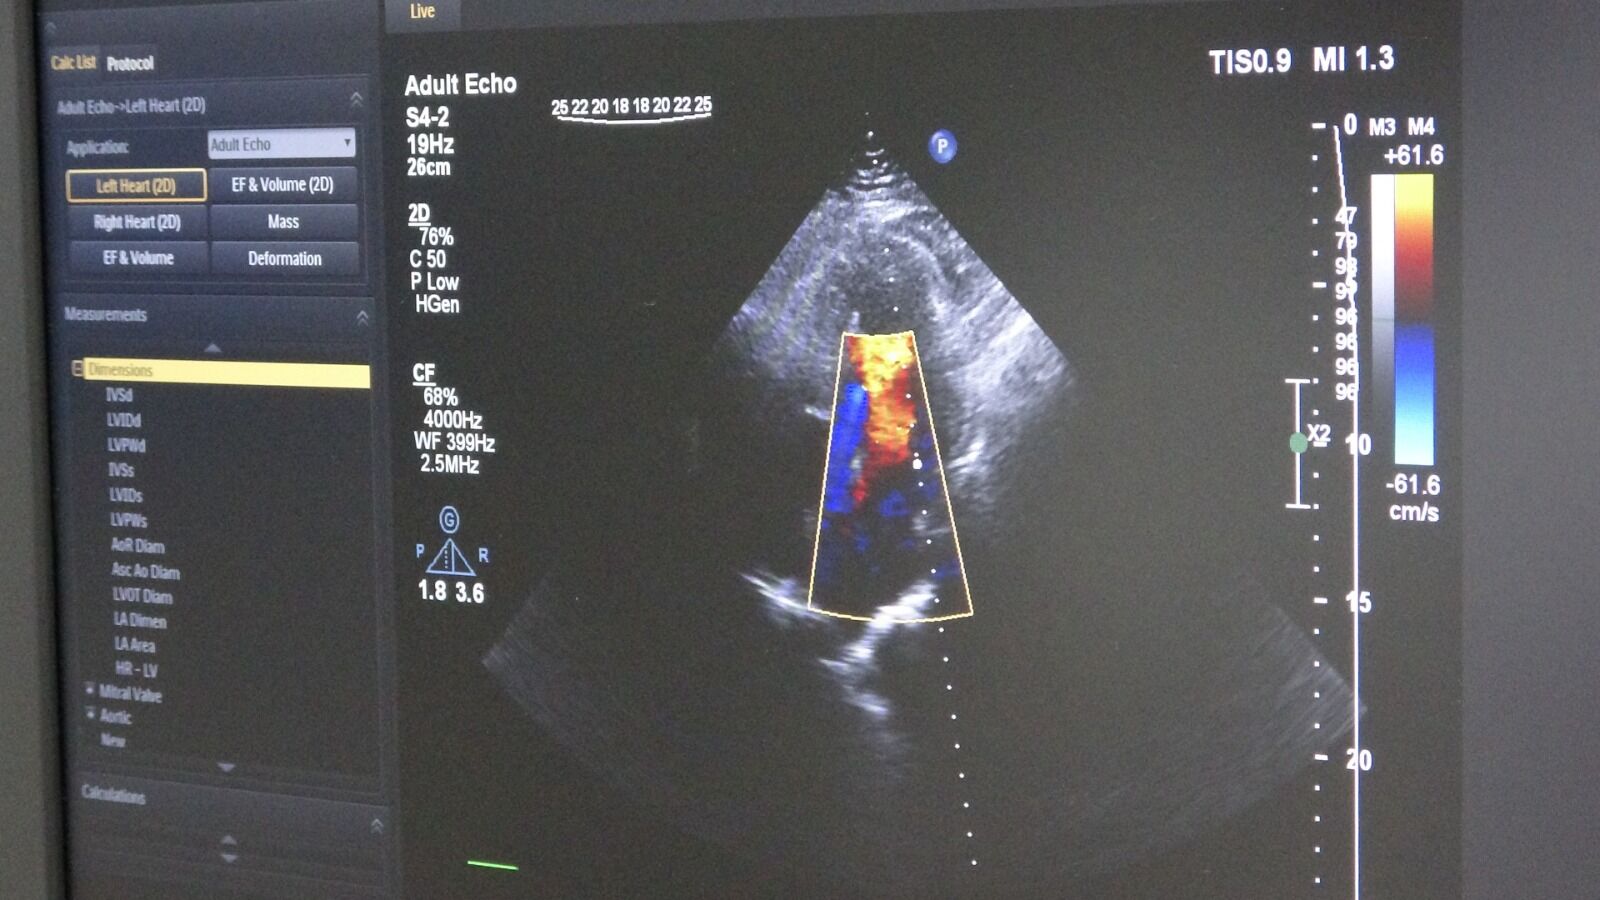

Tedavi sürecinde yalnızca klasik yöntemler değil, ileri teknolojik görüntüleme sistemleri de kullanıldı. İşlem öncesinde intravasküler ultrason (IVUS) ile damar yapısı detaylı şekilde incelendi. Ayrıca fraksiyonel akım rezervi (FFR) yöntemiyle darlığın kan akışına etkisi ölçüldü.

Bu teknikler sayesinde tedavi planı daha net belirlenirken, uygulamanın başarı oranı da artırıldı. Uzmanlar, bu tür ileri tanı yöntemlerinin doğru karar verme sürecinde önemli rol oynadığını belirtiyor.